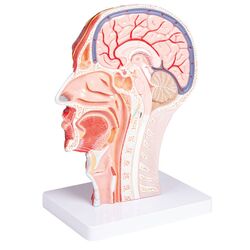

Priekinis ir vidurinis galvos pjūvis (reljefinis modelis) – Erler Zimmer

€155.12 Į krepšelį -

Pusė galvos, tikro dydžio – Erler Zimmer

€208.20 Į krepšelį